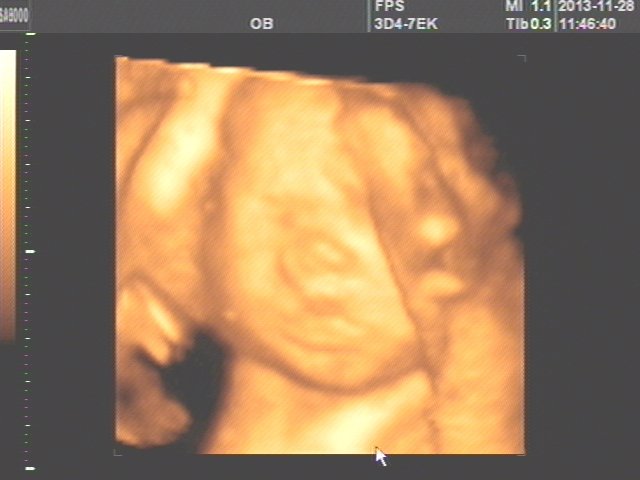

上面一张应该是脊柱,下面一张是宝宝的脸,成像的效果好差、、、不过你们家宝宝嘴唇有点厚,鼻子准头有肉,看来爸爸妈妈都是肉肉型身材劣录。下巴尖尖的,好可爱。 这样的照片你能猜到竞们吊是男是女我给射躬你写个服字!!!